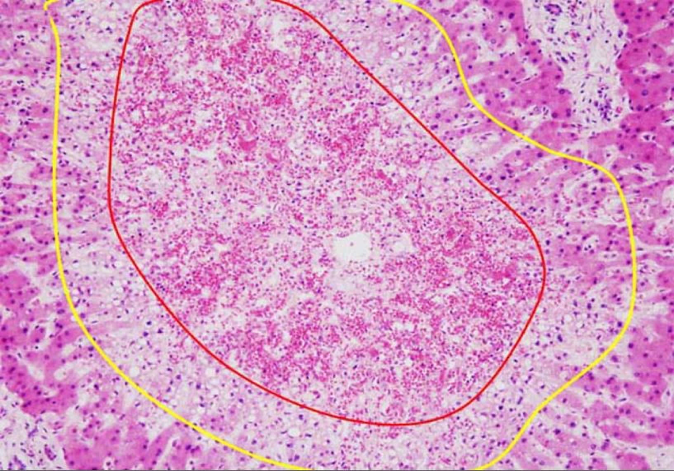

(3)病理变化: (1)急性肝淤血:肝脏体积增大,重量增加,包膜紧张,呈暗红色,质地较硬。 (2)慢性肝淤血:槟榔肝-切面呈红、黄相间的条纹,状似槟榔。 镜下:慢性肝淤血时,镜下见肝小叶中央静脉及其附近肝窦高度扩张淤血,肝细胞萎缩、坏死、崩解,小叶周边部肝细胞脂肪变性, |